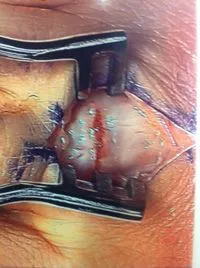

Pic during microfracture of tibial OCD.

Pics of nodules removed during scope.  A separate incision had to be made to remove the nodules due to the size.